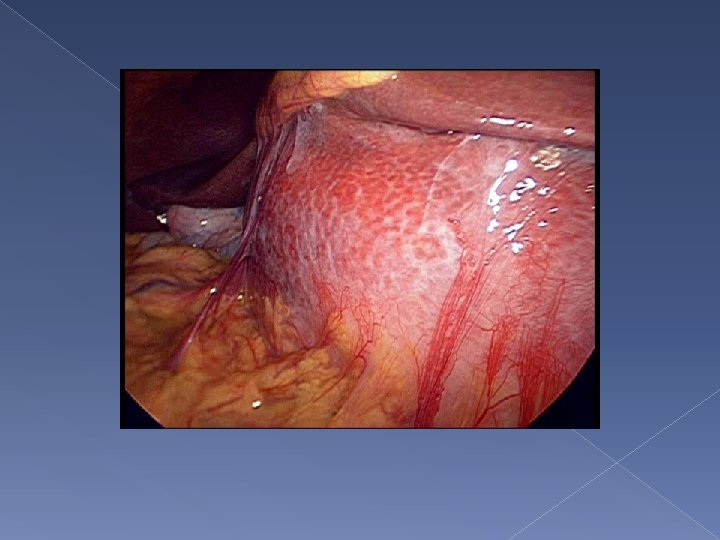

Progress − - Laparoscopy findings: No obvious peritoneal nodule 21 cm thick wall cystic lesion arising from left lobe of liver Laparotomy and left hepatectomy of segment 2/3 and part of segment 4 was performed

Thickness of wall around 1 cm, unilocular cyst 2. 4 L turbid yellowish fluid inside cystic lesion